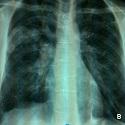

Embolie pulmonaire massive hydatique

Hicham Janah, Hicham Souhi

PAMJ. 2014; 19: 20. Published 09 September 2014